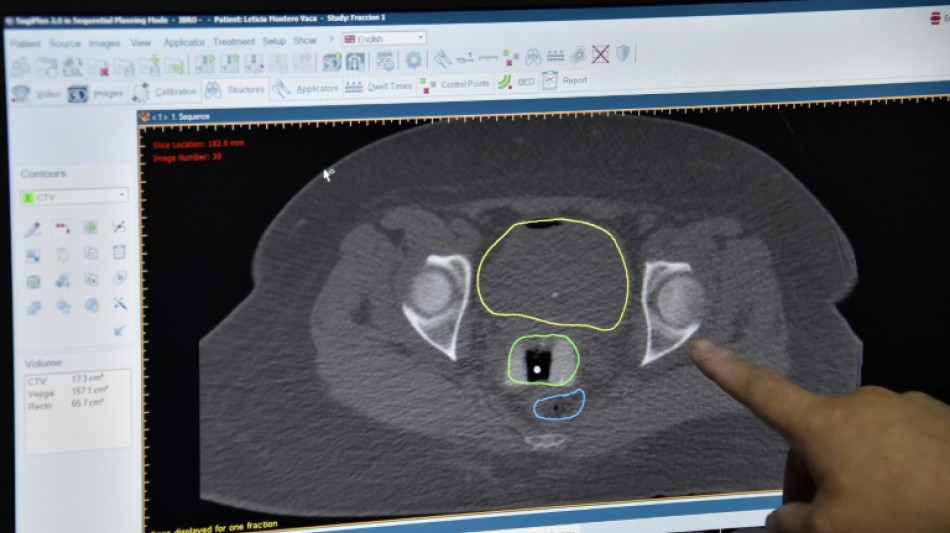

New cancer plan urged as survival improvements in England slow / Photo: AIZAR RALDES - AFP